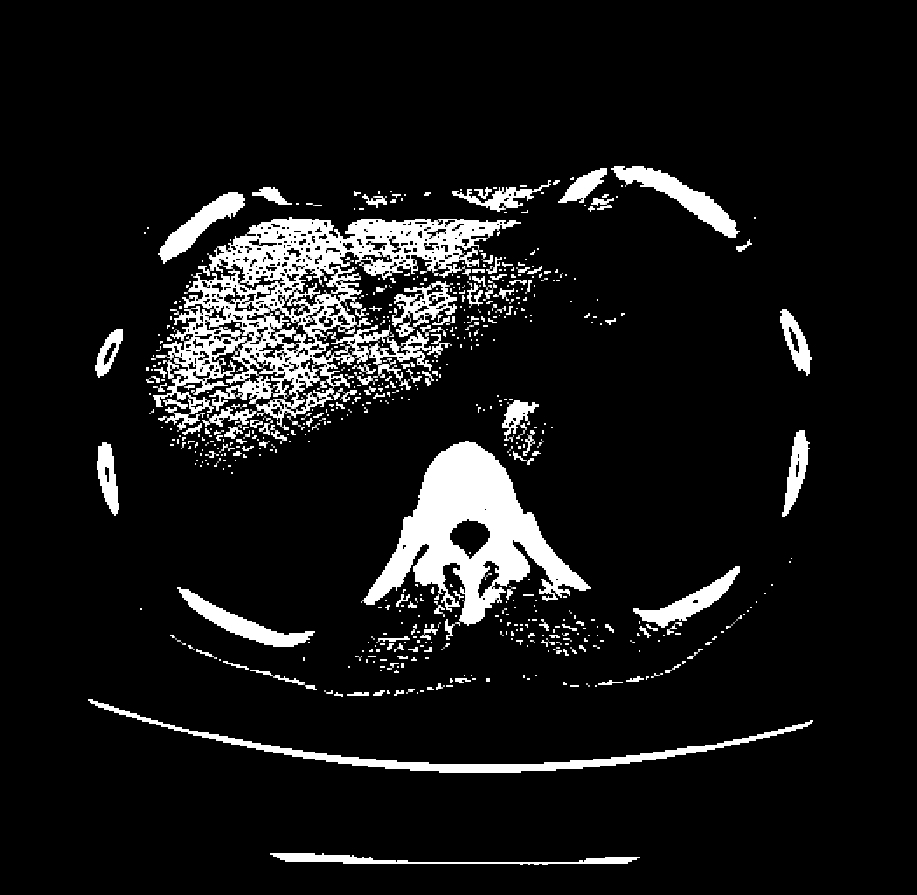

CT窗宽窗位(Window Width / Window Level)实例对比:同一胸部CT层面,通过调整窗宽和窗位,可以突出显示不同的组织结构

🎨 窗宽窗位:CT图像的"调色板"

由于人眼只能分辨约20-30个灰度级别,而CT的HU值范围从-1000到+3000,我们需要选择一个"窗口"来显示感兴趣的组织。例如:

- 肺窗(窗宽1500,窗位-600):适合观察肺部结构

- 纵隔窗(窗宽350,窗位50):适合观察心脏、血管

- 骨窗(窗宽2000,窗位300):适合观察骨骼 这就像是用不同的"滤镜"来突出不同的组织结构。